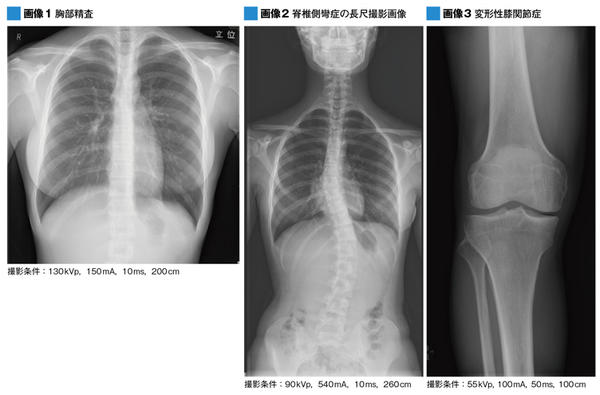

DigitalDiagnostでは,立位装置に専用の長尺撮影用衝立を組み合わせた“デジタル自動長尺撮影”のアプリケーションを搭載されている。長尺撮影は,脊椎側彎症の検査などで撮影されるが,従来は長尺に対応した特注のIPや透視撮影装置を使って数回に分けて撮影しており,撮影後の画像合成など手間と時間がかかっていた。DigitalDiagnostでは,専用衝立を使用して全脊椎の自動撮影が可能で,Auto Stitchingによって画像のつなぎ合わせ,画像間の濃度補正なども自動で行われる。松崎副技師長は,「当院でも長尺は透視装置を使って撮影していたのですが,多い時には1日10件以上の撮影があり,画像処理の作業などが負担になっていました。DigitalDiagnostでは,画像処理もほとんど自動で終了しますので,スムーズに検査が可能です」と高く評価する。

一般撮影検査を統括する松崎芳宏副技師長は,DigitalDiagnostの運用について,「通常の胸部・腹部撮影はもちろんですが,特にWPDの可搬型としての使い勝手の良さが発揮される四肢骨などの整形外科の検査や,低線量で高画質の撮影が必要な妊婦の骨盤計測などは,DigitalDiagnostを優先して使っています」と説明する。

フィリップスのFPDは,43cm×43cmで143μmの画素サイズを持ち,検出器にはCsl(ヨウ化セシウム)を用いた間接方式を採用している。FPDに使われているCslは量子検出効率(DQE)が高く,従来のフィルムやPCRに比べて線量を抑えた撮影が可能だ。同院では,CRでの撮影時の1/2程度の線量で撮影を行っている。平田技師長は,「一般撮影系をFPDに更新する時に重視したのが,線量の低減です。デジタルでは,線量をかければSNRが良い画像が得られますが,従来と同等の画質で線量を抑えることを優先に検討しました。患者さんの被ばくへの意識が高まっている状況では重要なことです」と,DigitalDiagnostのメリットを評価する。松崎副技師長は,FPDの感度が高いことで,通常の撮影はもとより,妊婦の骨盤計測の撮影で,線量を下げても診断が可能な画像が得られることをメリットに挙げている。